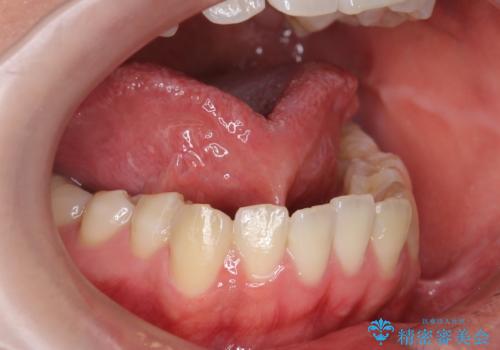

上唇と歯ぐきを結ぶひも(上唇小帯)が長く、上の前歯の間にまで伸びていました。

このままでは自然に前歯の隙間は閉じない可能性がありました。

そこで、上唇小帯切除術を行い、前歯の隙間が閉じにくくなるのを防ぎました。

術前に上唇をめくった状態で歯の間にあった、白い部分(貧血帯)が無くなったのが術後の写真でわかります。